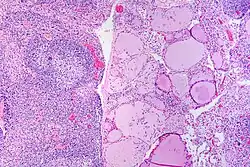

![]() | Hashimoto's thyroiditis | Hashimoto's thyroiditis with lymphoid infiltration. | Category: Hashimoto's thyroiditis with lymphoid infiltration | Hashimoto's thyroiditis |